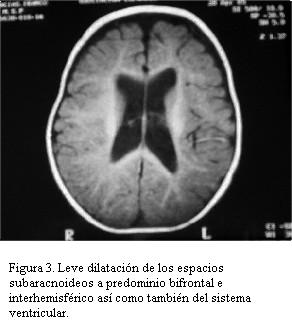

Resonancia magnética nuclear de cráneo que evidencia leve dilatación de los espacios subaracnoideos a predominio bifrontal e interhemisférico así como también del sistema ventricular, con pequeño quiste aracnoideo (figuras 2 y 3). No aumento en la señal en T2 a nivel del globo pálido, núcleo dentado cerebelar y sustancia blanca.